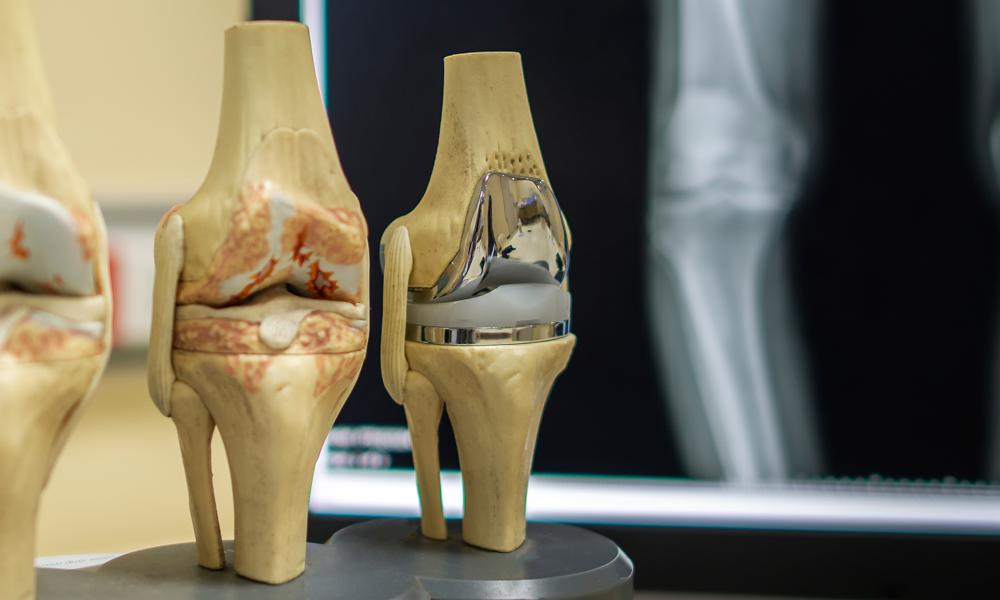

Knee replacement surgery (knee arthroplasty) is surgery to replace all or some of your knee joint. Your surgeon will replace damaged cartilage and bone with a prosthetic joint. It can take up to a year to recover fully after a knee replacement, but you’ll be able to resume some of your usual activities gradually as you heal.

جراحی تعویض مفصل زانو (آرتروپلاستی زانو) جراحی برای جایگزینی تمام یا بخشی از مفصل زانو است. جراح شما غضروف و استخوان آسیب دیده را با مفصل مصنوعی جایگزین می کند. بهبودی کامل پس از تعویض زانو ممکن است تا یک سال طول بکشد، اما میتوانید برخی از فعالیتهای معمول خود را به تدریج با بهبودی از سر بگیرید